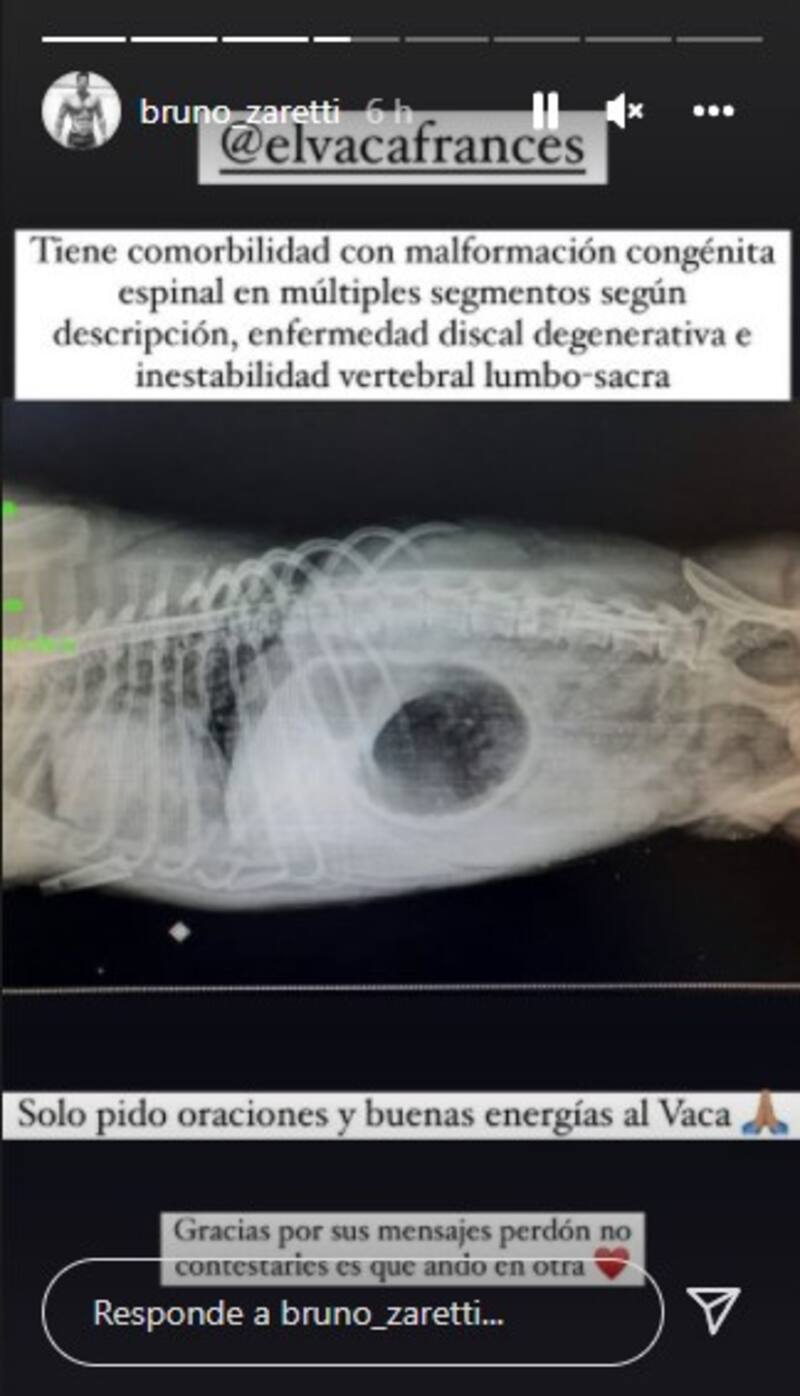

“Envíen sus buenas energías…” detalló en otro registro donde aparece acariciando y besando a su perrito, revelando posteriormente que sufrió una “comorbilidad con malformación congénita espinal en múltiples segmentos, una enfermedad discal degenerativa e inestabilidad vertebral lumbo-sacra”, pidiendo oraciones y agradeciendo el apoyo de sus seguidores.